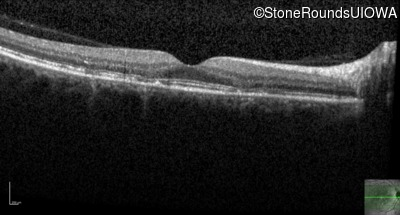

Optical Coherence Tomography - Right - 20/20

Exemplar / OCT Stack

OCT Stack